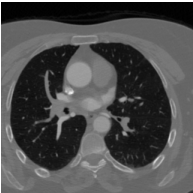

These typical loss functions define the loss of each pixel only on its true and predicted values, but not considering those of other pixels, and aggregate them by weighted averaging or summing without considering the spatial relations between the predictions. Since this type of definition is of local nature, these loss functions may not sufficiently impose a network to learn the shape of an object or the geometry between multiple objects, especially when the amount of training data is small. On the other hand, the ability of the network to learn the shape may be important for better segmenting the objects in medical images since these objects typically have an expected shape or a geometry due to their intrinsic characteristics. One example is the formation of the aortic arch and great vessels in a human body. The aorta and the large arteries and veins (also known as great vessels) are not randomly distributed over the human body. Instead, they are found in a particular geometry due to the human anatomy (Figure 1). Besides, they mostly seem as round objects on a 2D axial image since blood vessels are tubular in 3D. This anatomic information is indeed utilized by human annotators to locate these vessels and delineate their boundaries.

The proposed topology-aware loss function was tested on a dataset that contains CT scans of 24 subjects with prediagnosis of pulmonary embolism. The CT scans were acquired using a 128 slice Philips Ingenuity CT scanner with 1.5 mm slice thickness. A 60 ml of non-ionic contrast material (iohexol; generic name Opaxol) was introduced with a 100 ml saline chaser at 5 ml/s. The data collection was conducted in accordance with the tenets of the Declaration of Helsinki and was approved by Koc University Institutional Review Board (Protocol number: 2022.161.IRB1.064). We randomly split the 24 subjects into the training and test sets. The training set contains 2896 images of 16 subjects; 2234 images of 12 subjects were used to learn the network weights by backpropagation and 662 images of 4 subjects were used as validation images for early stopping. The test set comprises 1431 images of 8 subjects; note that the images of none of these subjects were used neither in the training nor for early stopping.